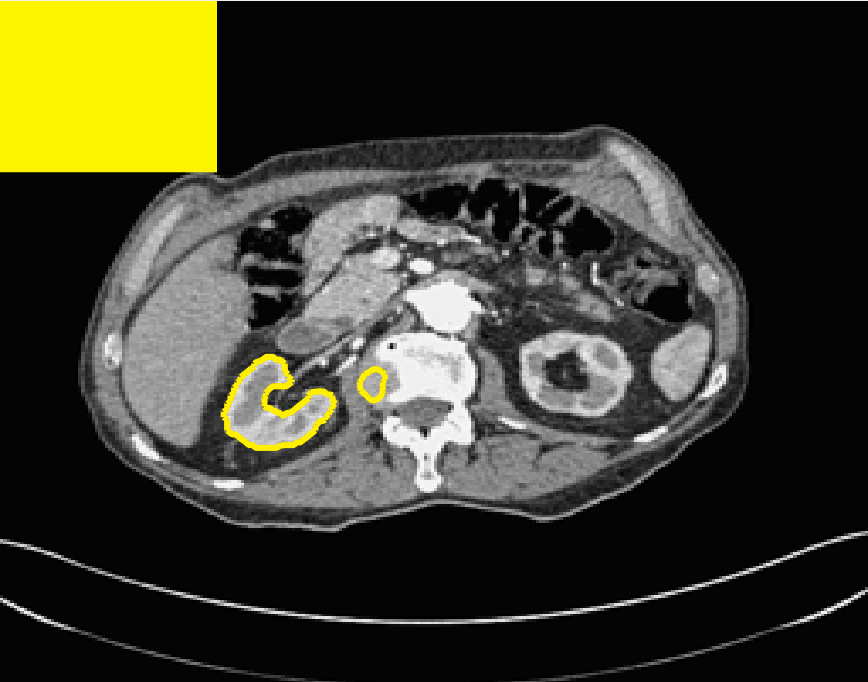

The motivation for this work comes from observing contradictions in using piecewise-constant intensity fitting terms in selective segmentation. Whilst good results are possible with this approach, the exceptional cases lead to severe limitations in practice. This is quite common in medical imaging as demonstrated in Fig. 1, where the target foreground has a low intensity. Given that the corresponding background includes large regions of low intensity, the optimal average intensities for this segmentation problem are and . For cases where , we see that by (1), almost everywhere in the domain . This means that it is very difficult to achieve an adequate result, without an over-reliance on the user input or parameter selection.

| (10) |

where is noise, is the characteristic function of the region , for respectively. The idea of selective segmentation is to incorporate user input to apply constraints that exclude regions classified as foreground, based on their location in the image. We use a distance constraint which penalises the distance from the user input markers. However, a key problem for selective segmentation is that for cases where the optimal intensity values and are similar, the intensity fitting term will become obsolete as the contour evolves. This is illustrated in Fig. 3. The purpose of our approach is to construct a model that is based on assumptions that are consistent with the observed image and any homogeneous target region of interest. A common approach in selective segmentation is to discriminate between objects of a similar intensity Rada:13 ; Geo ; CDSS . However, the fitting terms in previous formulations Klodt:13 ; Rada:13 ; Geo ; CDSS aren’t applicable in many cases as there are contradictions in the formulation in this context. We will address this in detail in the following section.

for and as defined in (33). This is consistent with respect to the intensities of the observed object and the concept of selective segmentation. In Fig. 3 we see the difference between CV and the proposed fitting terms for given user input on a CT image. For the CT image, the CV fitting terms are near 0 within the target region. This is despite there being a distinct homogeneous area with good contrast on the boundary. This illustrates the problem we are aiming to overcome. With the proposed fitting term this phenomenon should be avoided in cases like this. By defining as in (33) there is no contradiction if the foreground and background intensities of the target region are similar.